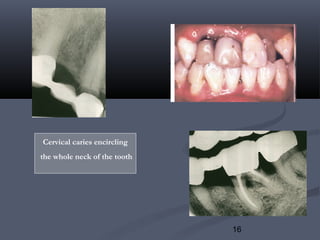

Cervical caries encircling

the whole neck of the tooth

III. Caries :III. Caries : ( Long term)( Long term)

1)1) Marginal cariesMarginal caries::

Generally begins at the surface and progresses inward. It may be theGenerally begins at the surface and progresses inward. It may be the

result ofresult of



incomplete caries removal, orincomplete caries removal, or

 a loose retainer that allows leakage.a loose retainer that allows leakage.

Space between the restoration & preparation allows cement solubilitySpace between the restoration & preparation allows cement solubility

resulting in gingival inflammation, caries and pulpal lesions.resulting in gingival inflammation, caries and pulpal lesions.

It isIt is detecteddetected by probing with a sharp explorer.by probing with a sharp explorer.

3)3) Root caries:Root caries:

Higher incidence in old age due to decreased salivary flow orHigher incidence in old age due to decreased salivary flow or

medication. such as beta blockers & diuretics.medication. such as beta blockers & diuretics.